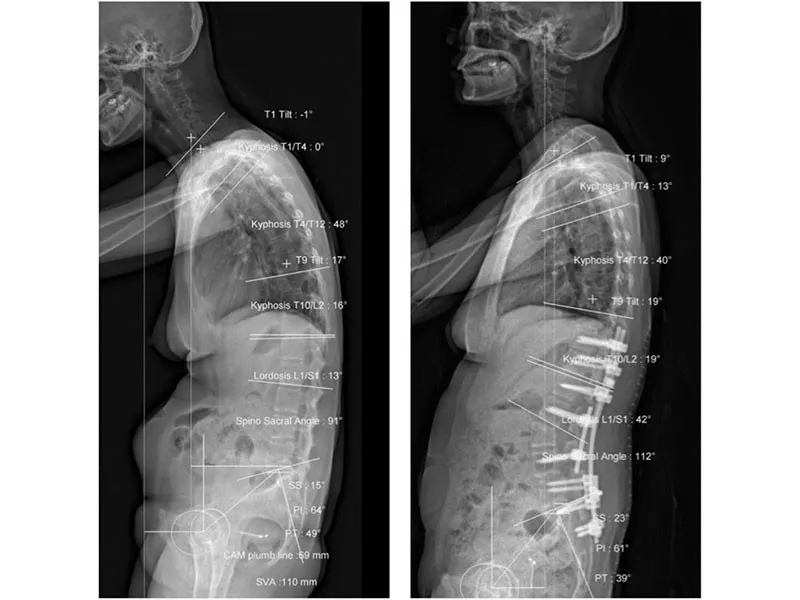

Sau khi hội chẩn, các BS quyết định tập trung nắn chỉnh vùng thắt lưng cho bệnh nhân bằng phương pháp đục xương sửa trục, bỏ chân cung ở đốt sống thắt lưng số 3 và cố định bằng bốn thanh nối dọc. Trong đó, hai thanh nối ngắn cố định chỗ đục xương sửa trục, hai thanh nối dài bắc cầu qua chỗ đục xương.

Theo BS Trực, đây là phương pháp mới được du nhập từ Úc, sử dụng bốn thanh nối dọc (nhiều hơn phương pháp thông thường chỉ có hai thanh) giúp tăng cường độ vững cấu hình cột sống. Cuộc mổ diễn ra nhanh hơn vì không cần thay thanh nối liên tục như trước. Bệnh nhân chỉ mất 1,2 lít máu, trong khi mổ thông thường sẽ mất 1,5-2 lít. Sau ca phẫu thuật kéo dài 4,5 tiếng đồng hồ, ngày thứ ba thì bệnh nhân đã đi đứng được, không còn biến dạng còng. Đặc biệt là có thể nhìn thẳng người khác để tự tin giao tiếp, không còn phải ngóc cổ lên như trước.

Tình trạng trước và sau khi phẫu thuật của bệnh nhân. Ảnh: HL

Ngoài ra, bệnh có biểu hiện cốt hóa, dính khớp từ dưới lên trên như dính vùng chậu trước rồi mới đến thắt lưng, ngực cổ. Ở bệnh nhân H., phim chụp X-quang không điển hình, khớp vùng chậu bị dính nhưng thắt lưng vẫn chưa dính hoàn toàn, cột sống ngực dính một ít và cột sống cổ dính hoàn toàn.